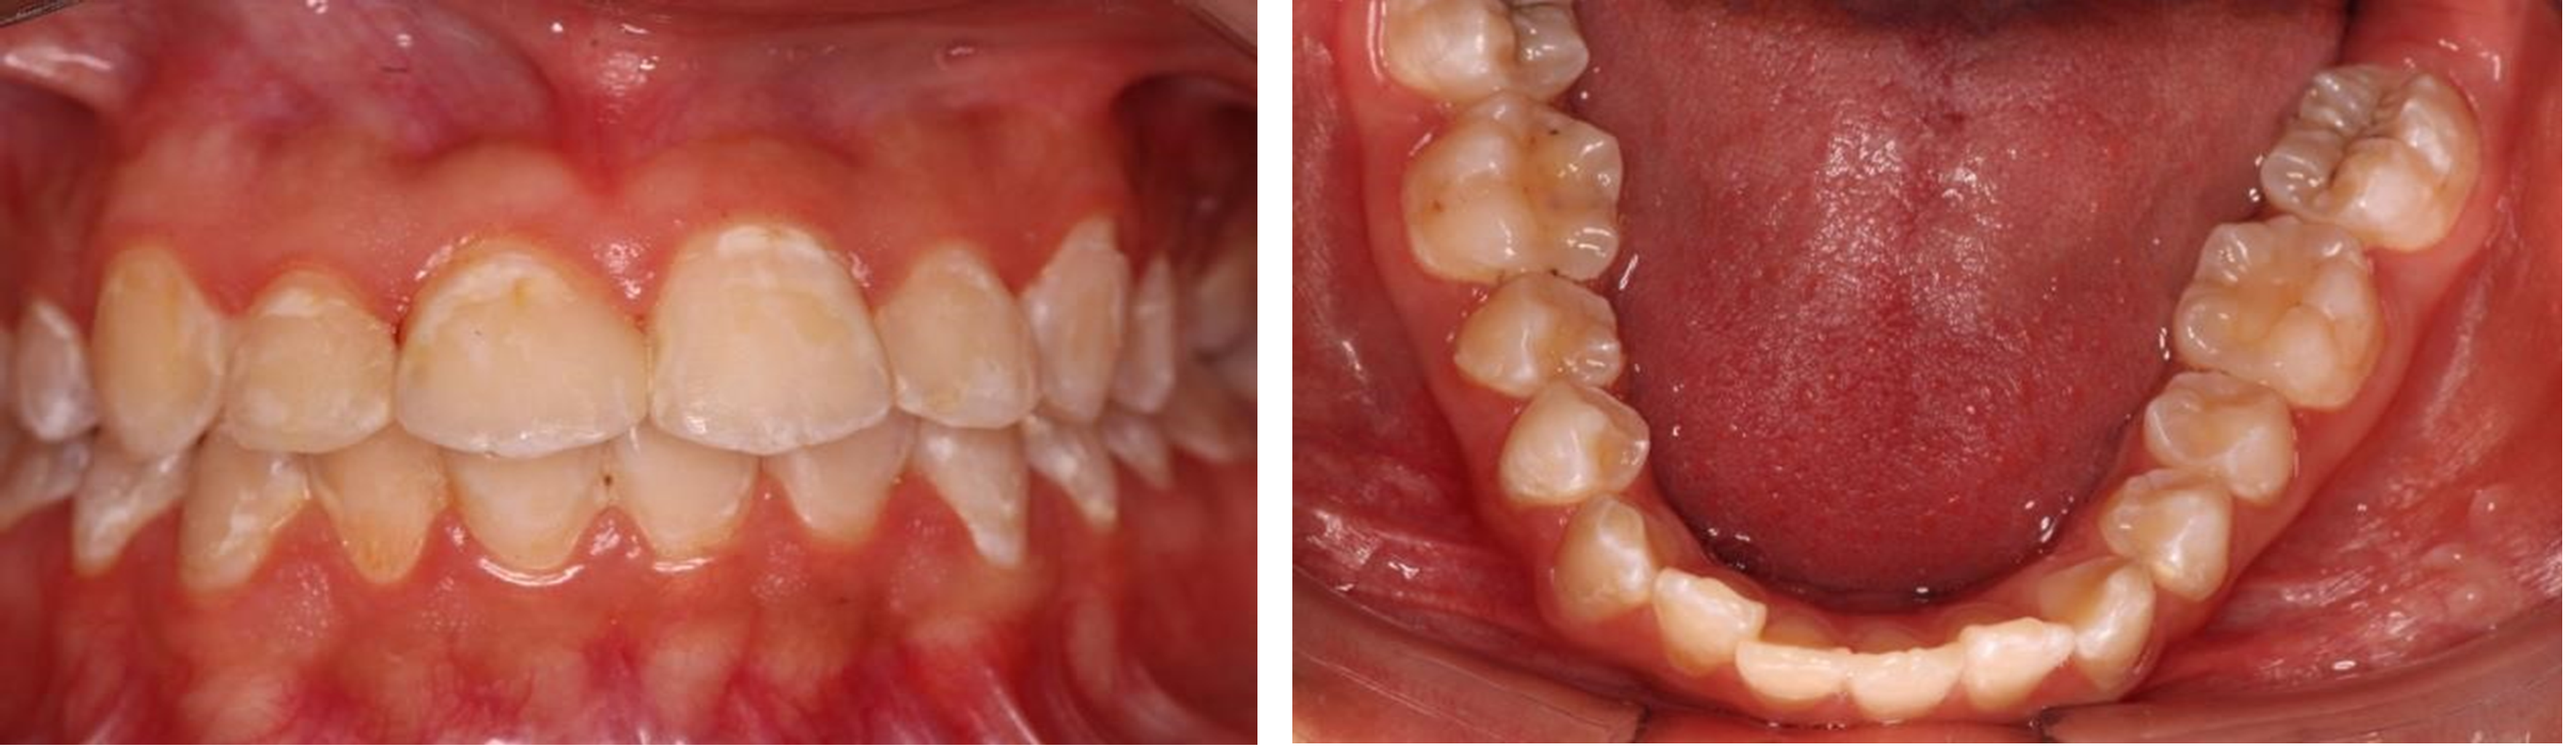

Figura 1. Estado de la dentadura del paciente 1

En la exploración física (figura 1), se diagnosticó una mancha blanca y placa bacteriana, primera manifestación de caries según el Sistema Internacional de Detección y Valoración de Caries (ICDAS 0). Como tratamiento, se decidió realizar la infiltración de resina con Icon, logrando la desaparición de algunas manchas y mejorando la integridad del esmalte.